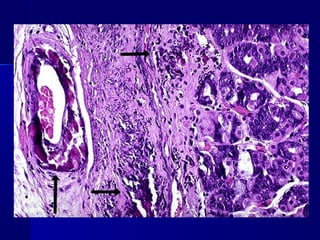

HIALINOSIS

DEGENERACIÓN HIALINADEGENERACIÓN HIALINA

 Término histológico descriptivo de lesión celular,

proporciona un aspecto homogéneo, vítreo y rosado

a las secciones histológicas rutinarias teñidas con

hematoxilina y eosina.

 En la hipertensión de larga duración y en la

diabetes mellitus, las paredes de las arteriolas,

especialmente en el riñón, se hialinizan, debido a la

proteína plasmática extravasada y al depósito de

material en la membrana basal.

DEGENERACIÓN HIALINADEGENERACIÓN HIALINA Término histológico descriptivo de lesión celular, proporciona un aspecto homogéneo, vítreo y rosado a las secciones histológicas rutinarias teñidas con hematoxilina y eosina.

• 83.

 En lahipertensión de larga duración y en la diabetes mellitus, las paredes de las arteriolas, especialmente en el riñón, se hialinizan, debido a la proteína plasmática extravasada y al depósito de material en la membrana basal.